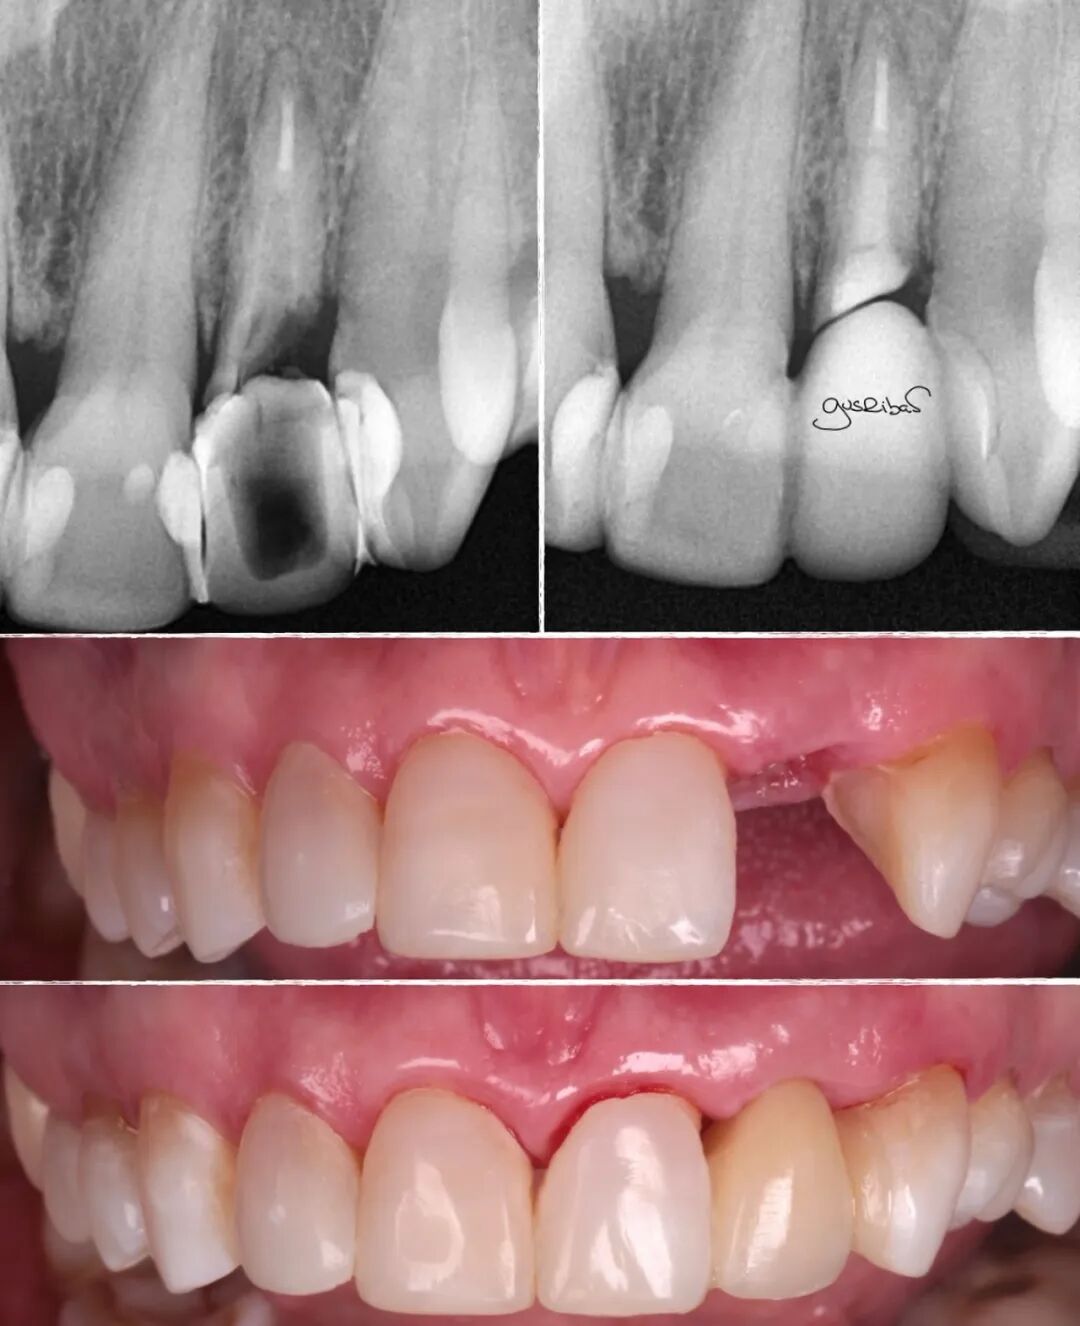

考虑到患者颌骨骨坏死的风险很高,没有进行任何侵入性手术,

在这种情况下,定期的牙周检查是必须且不可妥协的,

我使用粘接剂和复合树脂密封了根管,力求使其尽可能光滑和适应,

在邻牙上做了部分预备,立即封闭了暴露的牙本质,进行了数字化扫描,完成修复体的制作和美学调整,并用复合树脂进行了粘接。